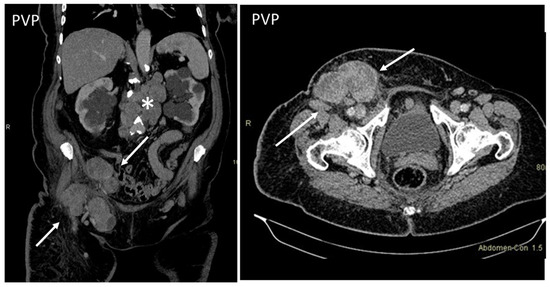

- Desmoplastic Small Round Cell Tumor (DSRCT): rare, highly aggressive sarcoma of adolescents, which primarily involves the serosal surfaces of the abdominal cavity infiltrating the abdominal wall [30,31,32]. Classic findings include bulky multiple, hypoattenuating, soft-tissue masses, with omental, serosal, and rectovesical involvement [31,32] and typical punctate or amorphous calcifications [32]. Modest heterogeneous enhancement is seen on arterial phase, without prolonged enhancement or portal washout [31,32] (Figure 10). On MR, DSRCTs are heterogeneously iso- to-hypointense on T1-w images, with hyperintense foci due to intratumoral hemorrhage [32].